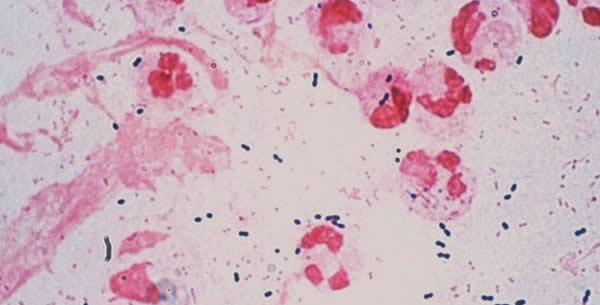

Sitni Gram (-) kokobacili, nepokretni posjeduju kapsulu, aerobi i fakultetivni anaerobi (ne stvaraju spore).

Hemophilus dukrei je uzrocnik seksualno prenosivog oboljenja sankr. U gnoju sankra se mogu naci Gram (-) bacili. Hemophilus dukrei zahtjeva samo faktor X. U organizam prodire zahvaljujuci ozljedama na kozi ili putem sluzi. Na mjestu ulaska formira se crvenilo. Nastale promjene su bolne, edematozne, otok regionalnih limfnih zlijezdi (ingvinalnih često).

Dijagnoza se postavlja uzimanjem gnoja iz ulceracije i prave se preparati koji se boje po Gramu.